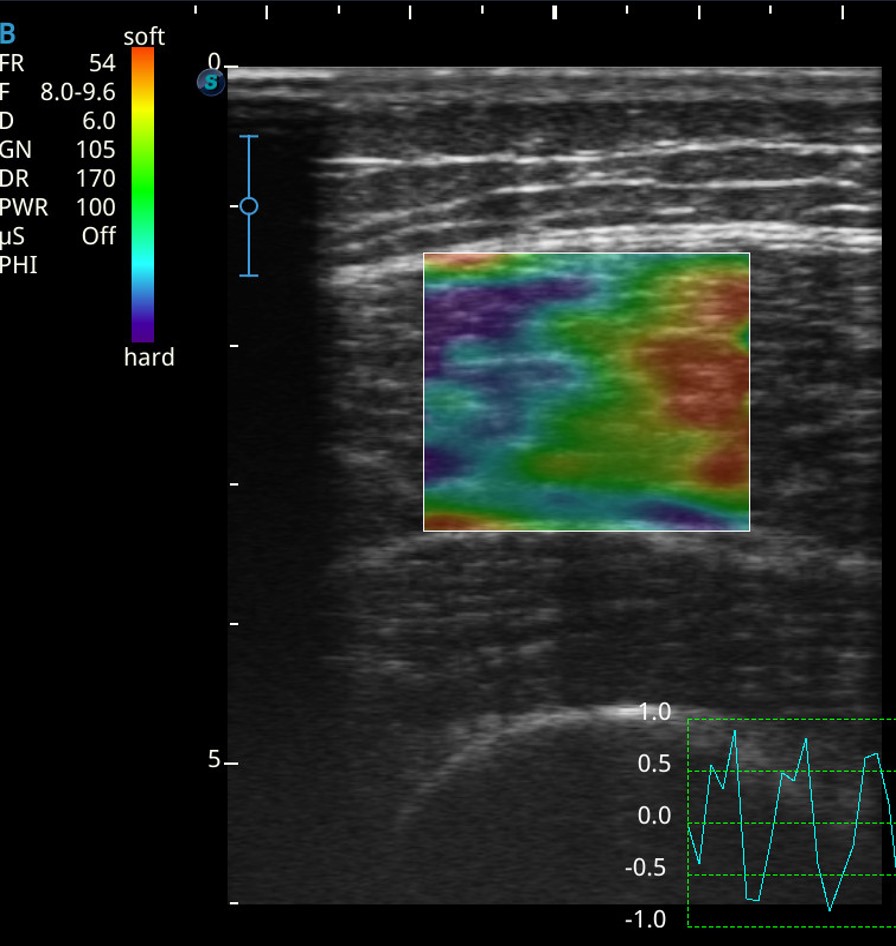

「形は力を産み、力は形を造る」という考え方から、アスリートに必要な骨格筋・腱複合体の形態や量と動作の関係について研究を行っています(骨格筋の筋厚、筋線維の羽状角、骨格筋の硬さ、動作分析[図1~4])。

図3